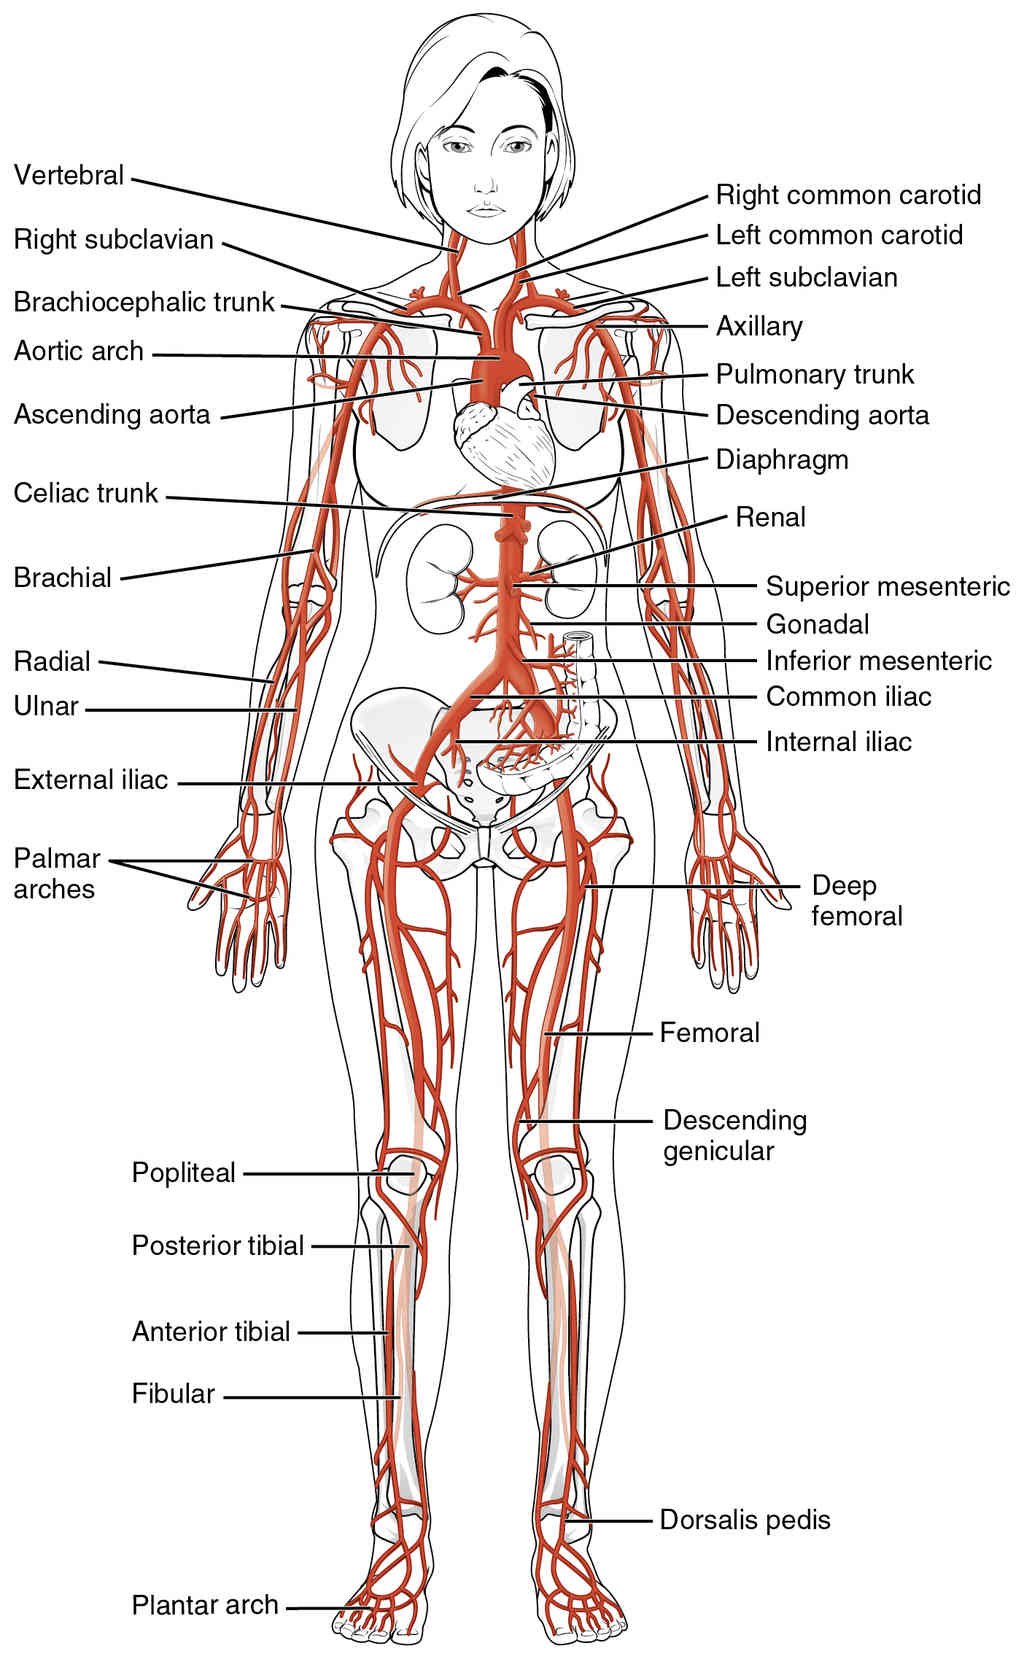

This page is under construction. For now, it is just a resource of the images found in the OpenStax Anatomy and Physiology Handbook. It wil slowly change into a revision tool. Each slide has a number. Use this to refer to the slide. When completed, it will have an unlabelled section, with labelled slides in parallel. On the unlabelled slides, write your answer and use the labelled slide to assess yourself. Keep track by also noting the number on each slide. Improvement at each attempt is important, more so than full marks on a first attempt.